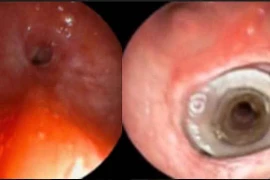

(khoahocdoisong.vn) - Mới đây, khoa Nội soi chẩn đoán và can thiệp, Bệnh viện Phổi Trung ương đã nội soi ống cứng đặt stent cứu sống bệnh nhân bị suy hô hấp cấp do hẹp khí quản, đe dọa tính mạng người bệnh.

Mắc bệnh phổi tắc nghẽn mạn tính và đã từng được chỉ định đặt ống nội khí quản thở máy, thời gian gần đây, bệnh nhân Trần Văn T. cảm thấy khó thở nhiều, nội soi phế quản bác sĩ phát hiện bệnh nhân bị xơ sẹo gây chít hẹp đường thở, có nguy cơ tử vong cao.